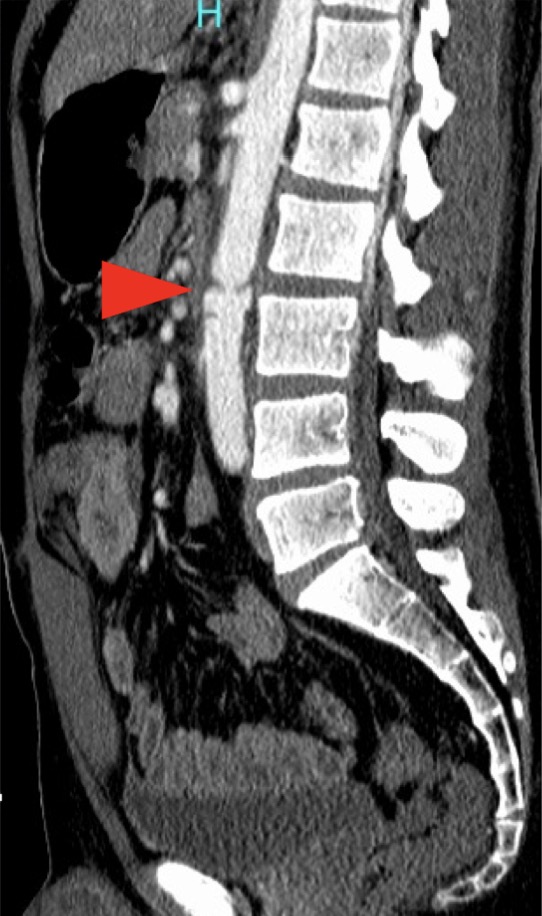

【シートベルト症候群 その5】 シートベルトによる⼤動脈解離は 腎動脈以遠(ZoneⅢ)で多い。 特にL2/3腰椎間に集中している⁉️(私⾒) 治療法は ⾎管内治療 or ⼿術 腸管内容物が腹腔内に漏れている場合 循環が安定しているなら、 術後感染しにくい ⾎管内治療(カテーテル治療)が第⼀選択となる💉

【シートベルト症候群 その4 】 腰椎の椎体前部に シートベルトが押しつけられると そこを⽀点として 椎体後部に上下⽅向の剪断⼒が発⽣し 後ろからパックリ割れる💥 これが『チャンス⾻折』 腹部を横断するシートベルトが 食い込むのが原因なので 第1-3腰椎の間に⽣じることが多い

【シートベルト症候群 その2 】 シートベルト症候群の機序↓ ベルトが上前腸⾻棘上を滑り 腹部に⾷い込む 三徴は ① シートベルト痕 ② 腸管損傷 ③ 腰椎⾻折 その他に 肺挫傷、肝損傷、脾損傷なども 起こりうる シートベルトに沿って 表面に外傷が発生するだけじゃない‼️😳

【シートベルト症候群 その1】 まず大前提ですが シートベルト装着は義務です👮 乗⾞時にシートベルトを装着しないと 致死率が ⼀般道路で3倍上昇❗️🚗 ⾼速道路で20倍‼️🏎️ しかし そのシートベルトを 装着していたがために 起きる外傷も存在する その名は 『シートベルト症候群』🚑